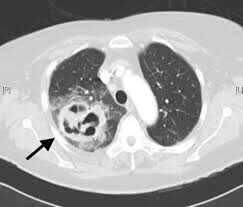

El absceso pulmonar es un estado de necrosis pulmonar secundaria a una infección y representa una lesión cavitada consecutiva a una destrucción parenquimatosa con supuración localizada; la necrosis central tiende a licuarse en el tejido pulmonar y ello establece una comunicación con el árbol bronquial.

El absceso pulmonar es casi siempre resultado de múltiples causas, entre ellas y con más frecuencia la aspiración de cargas bacterianas contenidas en secreciones procedentes de la vía oral, aspiración de cuerpos extraños, trastornos obstructivos por procesos neoplásicos, infartos sépticos, contusión pulmonar por traumatismo, parasitosis y neumonías necrosantes bacterianas.

- Aspiración: debido a que la aspiración de la vía aérea ocurre con más frecuencia en la posición supina, los abscesos por esta causa se presentan más veces en los segmentos inferiores y posteriores, como en el segmento apical y posterior del lóbulo superior derecho, seguido del segmento superior de los lóbulos inferiores y, menos a menudo, en el resto de los segmentos de los lóbulos inferiores.